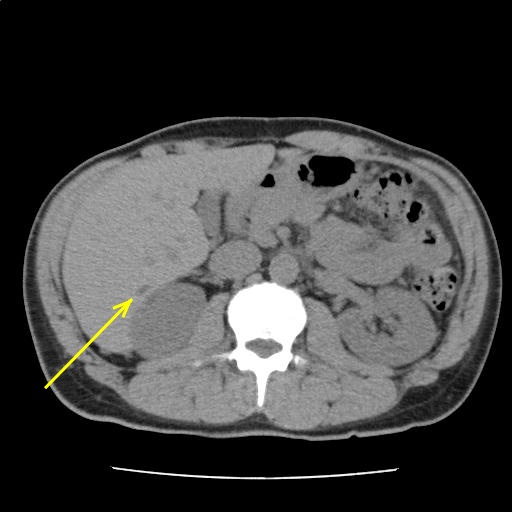

肝辺縁は整であり、明らかな慢性肝障害や肝硬変を疑う所見は認めない。

肝嚢胞を認める。

胆嚢、膵、腎、副腎、脾に特記すべき異常所見を認めない。

腹部に有意なリンパ節腫大を認めない。少量の腹水を認める。